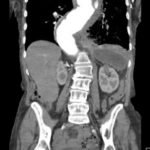

The patient’schest X-ray revealed a prominent mediastinum and opacification in the left middle and lower lung fields. The CT showed an aortic aneurysm extending from the thorax to the abdomen with rupture near T7 (blue arrow). It also showed periaortic hemorrhage with active extravasation (green arrow) likely secondary to a penetrating ulcer and bilateral pulmonary opacities concerning for hemothorax (pink arrow).